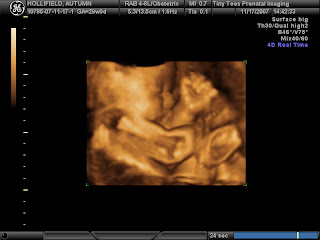

On another note, we're now 33 weeks along. Just 7 weeks until our due date of Feb. 2. I've started training my replacement at work and will now have a little more flexibility until I leave, which I am excited about. Cheyenne is pretty active lately. We can lay in bed and just watch her kicking and punching. It's really cool. She'll be here soon!